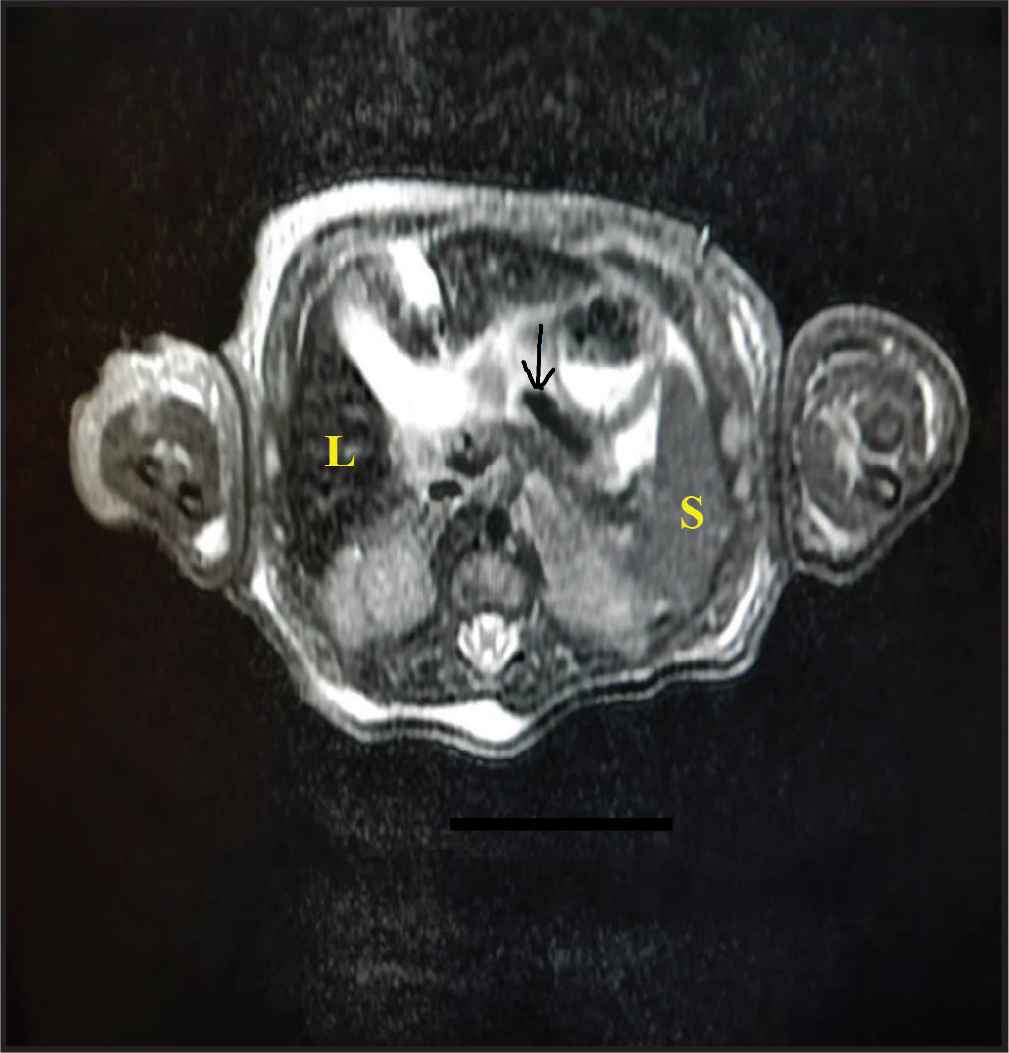

Abdominal Magnetic Resonance Imaging (MRI) was compatible with the diagnosis of NH. It showed clear siderosis that affected the liver and pancreas while sparing the spleen (Figure 1).

Abdominal magnetic resonance imaging. There was a dark T2 signal on the liver (L) and to a lesser extent, pancreas (arrow), compared to the skeletal muscles. The spleen (S) showed normal signal intensity. This was suggestive of neonatal hemochromatosis.